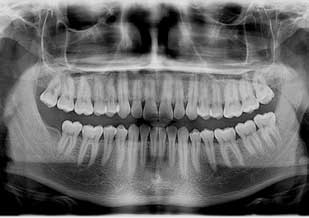

Radiografía panorámica (ortopantomografia)

Estudio radiológico de rutina donde se observan piezas dentarias, sus tejidos de soporte y estructuras anatómicas adyacentes. Es una radiografía bidimensional, es decir, una imagen plana de un objeto tridimensional.